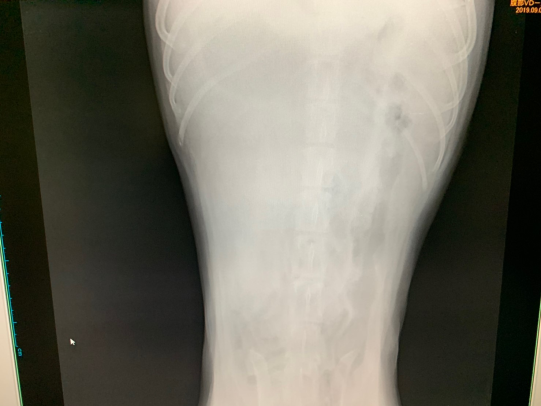

レントゲンで消化管が下腹部によっています。

腹水も確認でき、貧血とアルブミン(1.8)の低下が認められました。